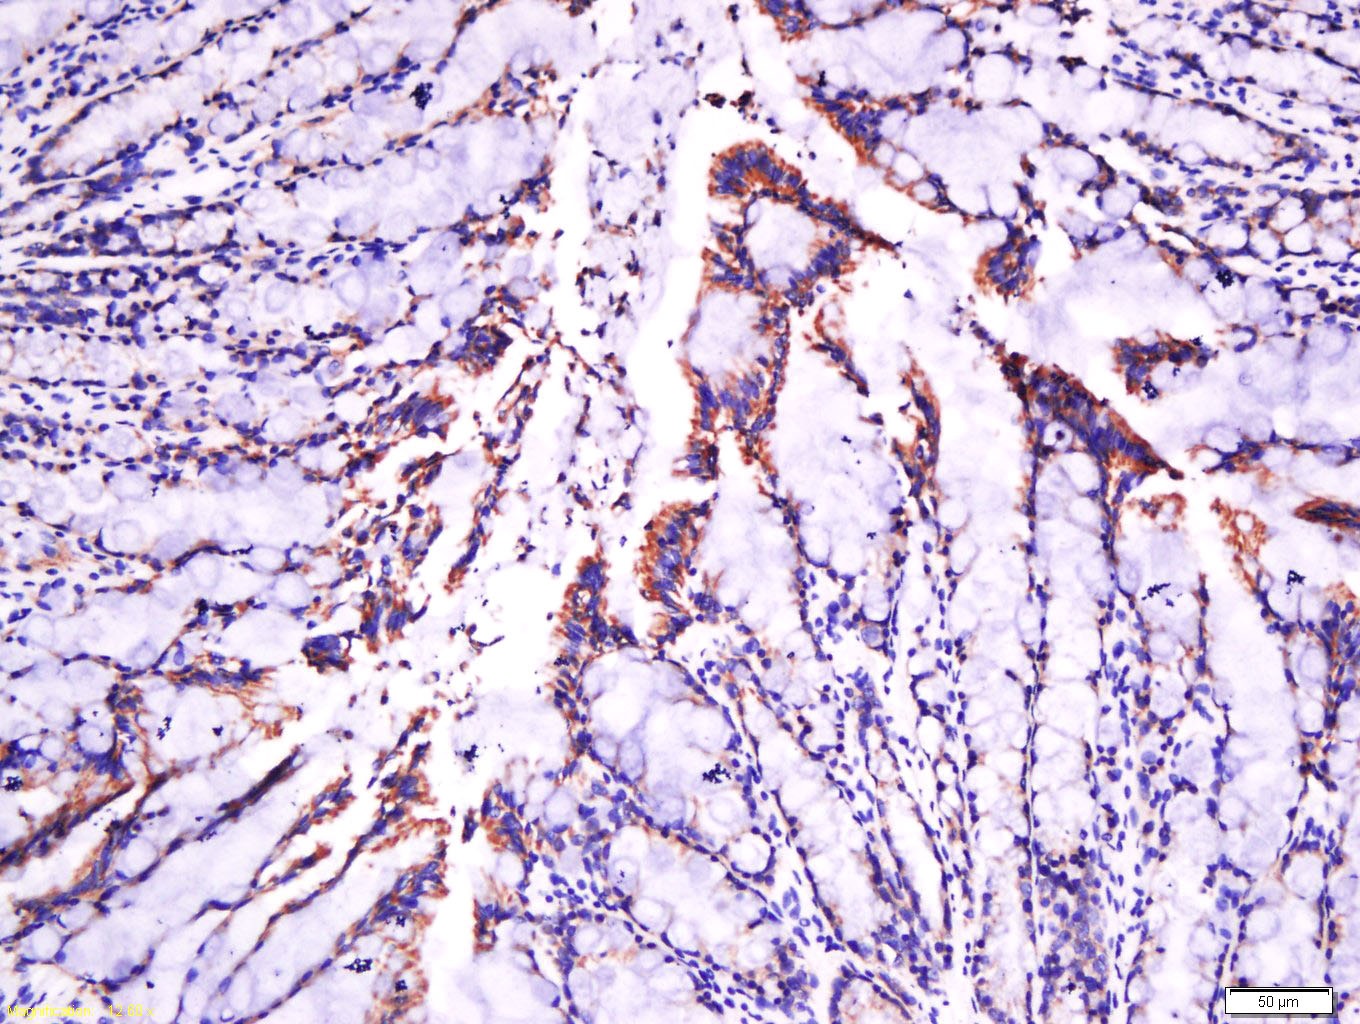

1. Tissue/cell: rat intestine tissue; 4% Paraformaldehyde-fixed and paraffin-embedded;

Antigen retrieval: citrate buffer (0.01M, pH6.0), Boiling bathing for 15 min; Block endogenous peroxidase by 3% Hydrogen peroxide for 30 min; Blocking buffer (normal goat serum) at 37°C for 20 min;

Incubation: Anti-laminin Polyclonal Antibody, Unconjugated (TMAB-01044) 1:500, overnight at 4°C, followed by conjugation to the secondary antibody and DAb staining.